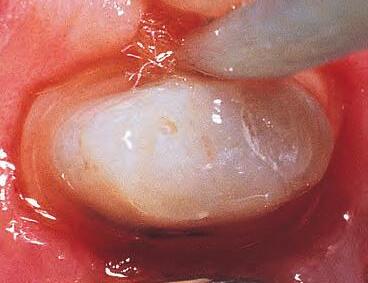

1. Well-healed tissue 2 weeks post-op.

Note: Perfect sulcular fluid control is mandatory if bonding and luting is adjacent to gingival sulcus.1

MICROLEAKAGE

PROVISIONAL REMOVED STAINING

2. Upon removing some of the composite, the extent of leakage is more evident. Contamination has occurred, therefore compromising the seal. Hemostatic, blood, sulcular fluid, saliva, and byproducts from anerobic bacteria can be sources of contamination. Retreatment is necessary.

1. For restorations, Astingedent™ X hemostatic and Ultrapak cord are ideal for controlling blood and sulcular fluids and can also protect tissue from burs. Use a firm air/water spray to remove excess hemostatic solution.

1. Packing Ultrapak cord quickly displaces tissues and improves access for indirect veneer luting.